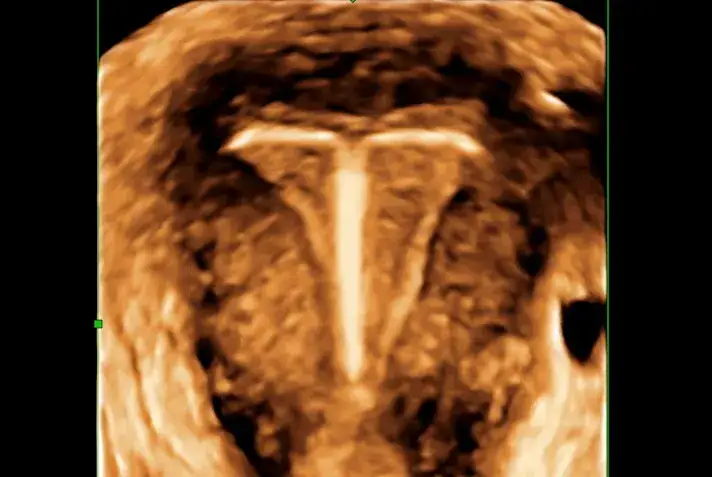

W diagnostyce zatkania przewodów żółciowych kluczowe są różne badania laboratoryjne oraz techniki obrazowe. Badania krwi, takie jak testy na bilirubinę, pozwalają ocenić poziom bilirubiny we krwi, co jest istotne w przypadku podejrzenia żółtaczki. Dodatkowo, badania enzymów wątrobowych mogą wskazywać na uszkodzenie wątroby związane z zablokowaniem przepływu żółci. W przypadku, gdy wyniki badań laboratoryjnych są niepokojące, lekarze często zalecają wykonanie badań obrazowych.

Najczęściej stosowanymi technikami obrazowymi są ultrasonografia oraz rezonans magnetyczny (MRI). Ultrasonografia jest nieinwazyjną metodą, która pozwala na wizualizację kamieni żółciowych oraz oceny stanu dróg żółciowych. Z kolei MRI dostarcza bardziej szczegółowych obrazów, co jest szczególnie pomocne w przypadku podejrzenia zmian nowotworowych. Oba te badania są kluczowe dla postawienia prawidłowej diagnozy i podjęcia dalszych kroków w leczeniu.